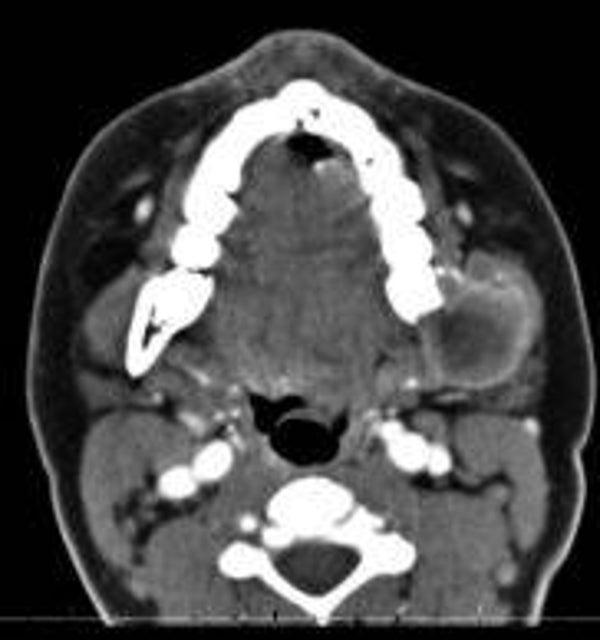

Before and after treatment images

Pathology progress

Healing Progress